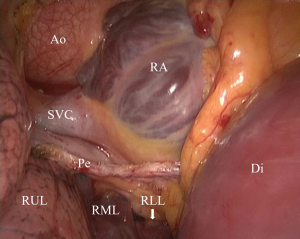

For pleurectomy to commence, apnea had to last for 1 min in both groups, and the bronchial cuffs in both groups were then inflated to start lung isolation. After the retractor was fixed between the ribs, group M’s surgical field exposure was evaluated (Figure 2). If the inflated right upper lobe affected the ascending aorta and aortic root’s surgical exposure, mechanical ventilation was suspended for pericardial traction (if hypoxemia occurred during this period, manually controlled DLV with a small tidal volume was applied to assist the pericardial traction). The surgical field exposure was reassessed after restarting mechanical ventilation. If the exposure was still unsatisfactory, the SLB was changed to right lung isolation (Figure 3). Times of intraoperative dislodgement or loss of seal were also recorded.

BB was previously used for lung isolation in MICS (10), with only the right main bronchus blocked to achieve the right lung collapse. This might fail to treat possible hypoxemia after CPB, whereas SLB can notably increase the oxygenation index (11). In the case of robot-assisted coronary artery bypass grafting, the patient can encounter severe hypoxemia when the BB is used to isolate the left lung. Subsequently, BB’s cuff was placed forward into the left upper lobe bronchus for SLB, after which hypoxemia was resolved and it was possible to proceed with the operation (12). We first attempted to apply SLB in MICS through right lateral mini-thoracotomy with BB blocking the bronchus intermedius (Figure 5).